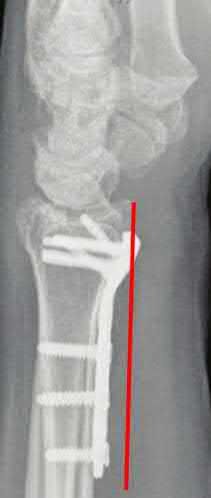

Question 6:

A 45-year-old manual laborer presents with chronic radial-sided wrist pain, recalling a fall on an outstretched hand 5 years ago. Imaging shows a scaphoid nonunion with radioscaphoid and capitolunate arthritis, but the radiolunate joint remains completely preserved. This describes which stage of Scaphoid Nonunion Advanced Collapse (SNAC), and what is a standard surgical option?

Correct Answer: SNAC Stage 3; Four-corner fusion with scaphoid excision

Explanation:

The progression of SNAC wrist is predictable. Stage 1 involves arthritis at the radial styloid; Stage 2 involves the entire radioscaphoid joint; Stage 3 involves the capitolunate joint; Stage 4 involves the radiolunate and/or entire carpus. Because the radiolunate joint is preserved in Stage 3, a four-corner fusion (capitate, hamate, lunate, triquetrum) with scaphoid excision is the standard salvage procedure. Proximal row carpectomy is contraindicated due to capitolunate arthritis.